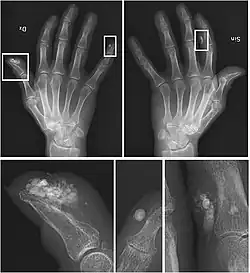

Se debe realizar una historia clínica detallada y solicitar una analítica general que incluya función renal, sodio, potasio, calcio corregido, fósforo y el producto de ambos, amilasa, lipasa, creatina cinasa (CK), aldolasa, paratohormona (PTH), enzima convertidora de angiotesina (ECA), vitamina D, autoinmunidad, hemograma, gasometría (bicarbonato, pH), orina de 24 horas con excreción de calcio y fósforo.

También se deben hacer pruebas de imagen como radiografías y TAC (tomografía axial computarizada) en las que se puedan objetivar las calcificaciones.

El diagnóstico definitivo es histopatológico: material granular amorfo con calcio.

Los depósitos suelen hallarse en áreas con degeneración del colágeno o tejido adiposo, en relación con trastorno subyacente.